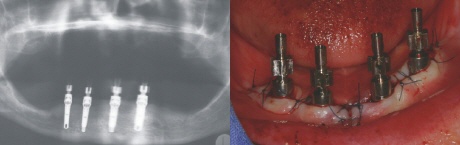

Implantation

Ohne großen Aufwand konnten in örtlicher Betäubung vier Implantate eingebracht werden (links im Röntgenbild).

Direkt in der Sitzung werden sogenannte Abformpfosten auf die Implantate geschraubt (rechts im Bild), um deren Position für ein Gipsmodell zu erfassen.